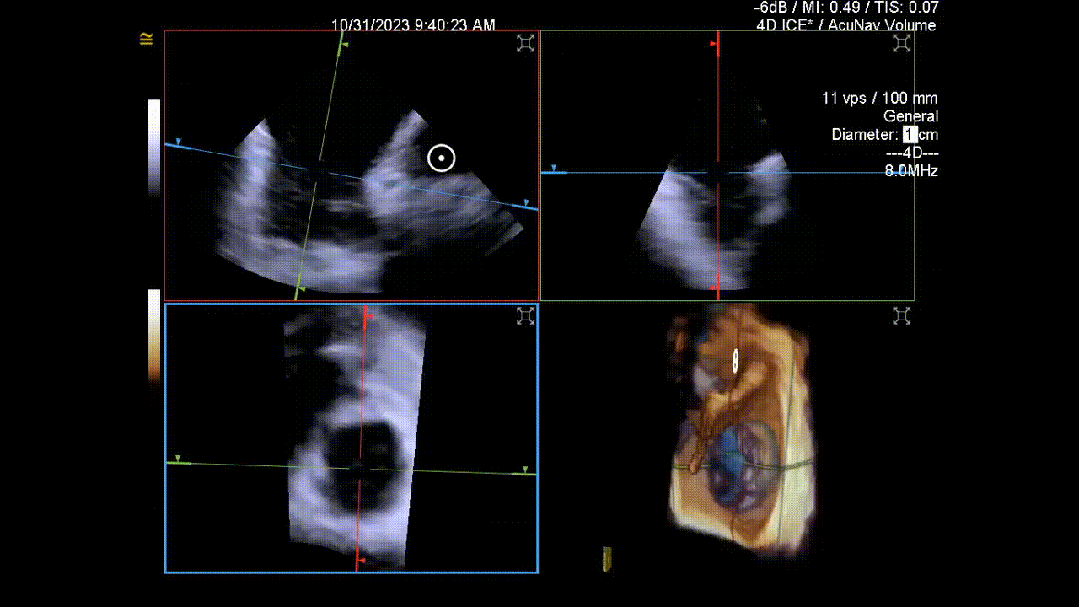

当TEE成像困难时,三维心腔内超声心动图(3D-ICE)可作为备选成像工具。有三种不同的三维心内超声心动图设备可供选择,包括AcuNav Volume (Siemens Healthiness)、VeriSight Pro(Philips)和NuVision(Biosense Webster),每种导管直径和视野略有不同(见图9、视频4和视频5)。3D-ICE可作为经导管三尖瓣不同介入手术(包括TEER和经导管瓣环成形术)中TEE的辅助术中引导。然而,3D-ICE仅在亚太地区(如香港)非常有限的机构可以使用,且导管价格昂贵(4,500至5,500美元)。